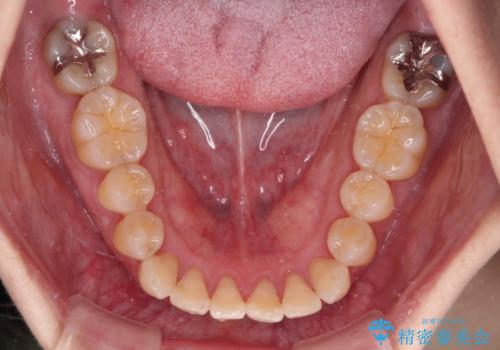

- 前歯のデコボコと口元の突出感を気にして来院された患者様です。

上下前歯がくちばしのように突出していたため、上下左右の第一小臼歯4本を抜歯し、ワイヤー装置にて矯正治療を行うこととしました。

上顎骨に対して下顎骨がやや前方位に位置しているため、歯肉退縮を回避するために下顎前歯をあまり内側に移動させることができない状況でしたが、十分に口元の突出感を改善することができました。